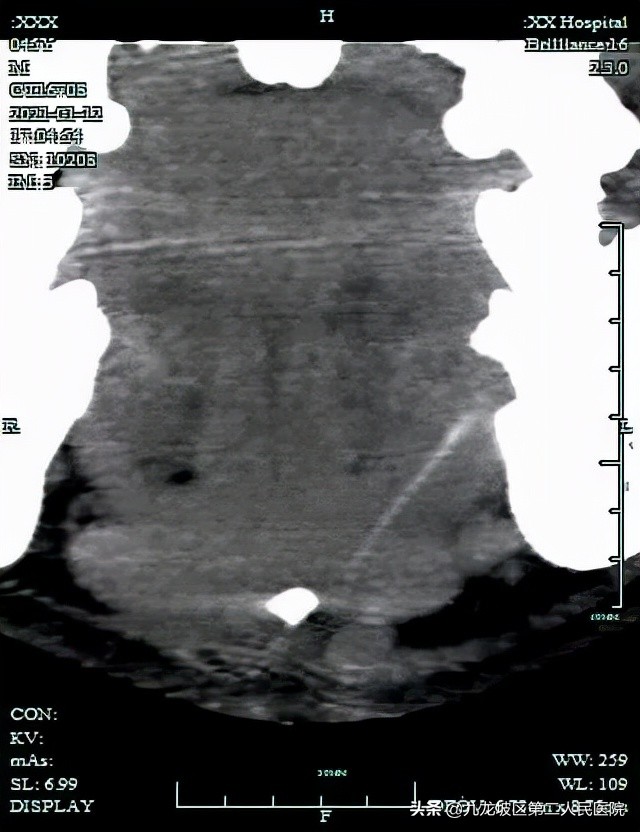

经过和放射科的一番讨论,最终决定对病人进行多层螺旋CT联合瘘管造影检查。

“CT扫描显示病灶位于舌骨上方,且与舌骨无明显关系,所以我们排除了甲状舌管瘘。”医生说,“在影像后处理工作站中行多种后处理,病灶全貌才得以显现。我们采用最大密度投影,最终发现颏下脓肿来自D7磨牙根尖脓肿,瘘管管径仅1mm。”